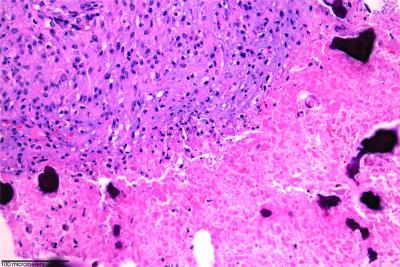

Verena Staedtke, M.D., Ph.D., a Johns Hopkins neuro-oncology fellow, first tested the spore injection in rats with implanted brain tumors called gliomas. Microscopic evaluation of the tumors showed that the treatment killed tumor cells but spared healthy cells just a few micrometers away. The treatment also prolonged the rats' survival, with treated rats surviving an average of 33 days after the tumor was implanted, compared with an average of 18 days in rats that did not receive the C. noyvi -NT spore injection.

The dogs showed a variety of anti-tumor responses and inflammatory side effects.